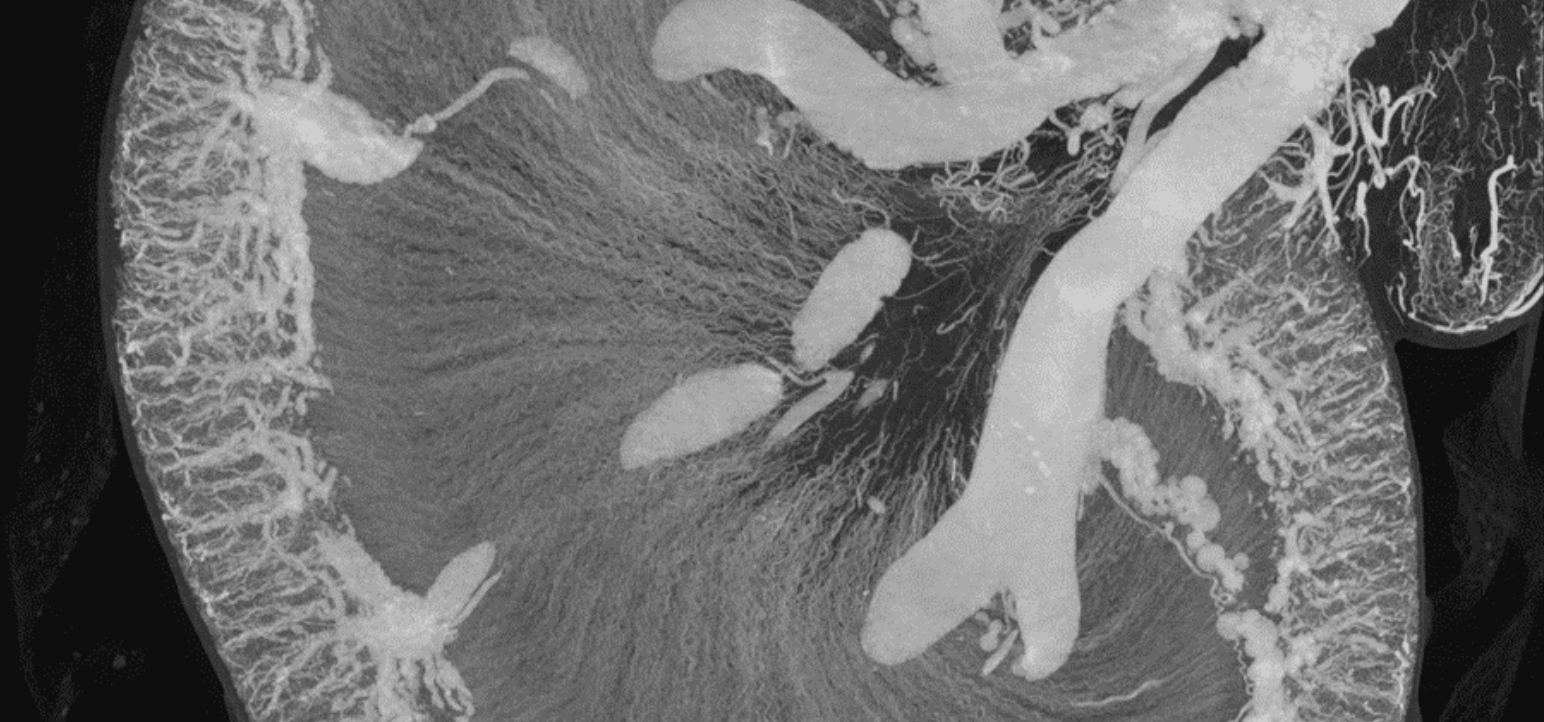

Vasculature perfusions, infiltrated rabbit renal tubules

Vascular exploration of small animals requires very high spatial resolution in order to differentiate large as well as small vessels. The SkyScan micro-CTs provide the necessary high resolution 3D volumetric data suitable for analysis, quantification, validation, and visualization of results.